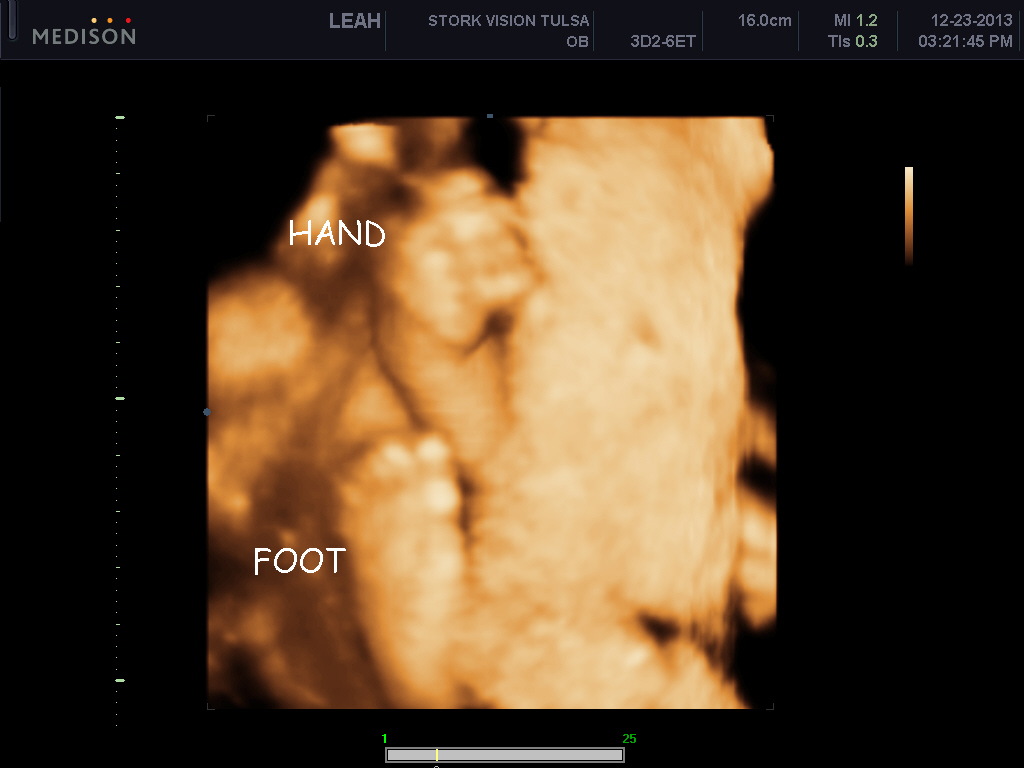

I want to AW my sons 3d ultrasound! :) PIP heavy

He's freaking adorable! These are my favs out of about 70 pictures..

imageimageimage